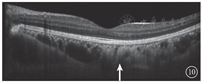

患者女,26岁,为例1患者女儿。因母亲诊断为Ⅰ型神经纤维瘤病于2018年1月16日到吉林大学第二医院眼科就诊。无异常视觉主诉,否认除母亲以外其他家人有相关症状体征。患者颜面及肢体见多个神经纤维瘤及咖啡斑(图6)。眼科检查:双眼视力1.0。双眼虹膜见Lisch结节(图7)。双眼眼前节大致正常。眼底彩色照相可见其黄斑区末梢血管略扭曲(图8)。红外眼底成像、EDI-OCT及ICGA检查表现与其母亲相似(图9,图10,图11)。诊断:Ⅰ型神经纤维瘤病。

Ⅰ型神经纤维瘤病大多存在脉络膜结节,常规眼底检查和眼底彩色照相不能发现病变[5]。本文例2患者仅在彩色眼底像中可见双眼黄斑区末梢血管略扭曲,这样的异常血管只存在于视网膜浅层,常见于颞上、颞下静脉的二三级分支,且在FFA上无荧光素渗漏;在EDI-OCT上可见对应位置的脉络膜毛细血管层萎缩以及脉络膜大血管缺失。但脉络膜大血管在解剖结构上是缺失还是仅仅被压缩,尚无定论。对于这样的脉络膜结节,最有效的检查手段是红外眼底成像。这些脉络膜结节由包绕神经纤维轴突增生的施万细胞和黑色素细胞组成,由于黑色素细胞对红外线的反向散射作用,病灶在红外眼底成像上表现为强反射。另外,脉络膜结节的致密结构降低了可吸收红外线的血红蛋白和水等血液成分的含量,病变区域红外线吸收得相对减少也是红外眼底成像上反射增强的原因之一[6]。